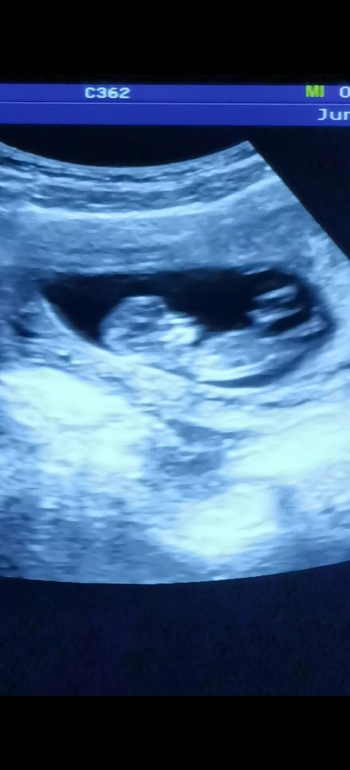

1 скрининг 😍 погадаем какого пола?)

Эмоции переполняют... Токсикоз закончился в 10 недель и я страшно переживала все ли в порядке, но решила дождаться 1-го скрининга) попала к своей любимой узистке и вместе с врачом наблюдали минут 10 со всех сторон как крошка подпрыгивает, шевелит ручками, ножками, трогает личико и протягивается😍 я и смеялась и плакала и все засняла на видео на телефоне, теперь целый день пересматриваю 😄 уже так хорошо видно лицо... Мне даже кажется, что уже копия муж 😁😍😍😍 на фото где видно личико, ручкой закрывает глазик сверху) узист сказала, что похожа на девочку 🤗а вы что думаете?